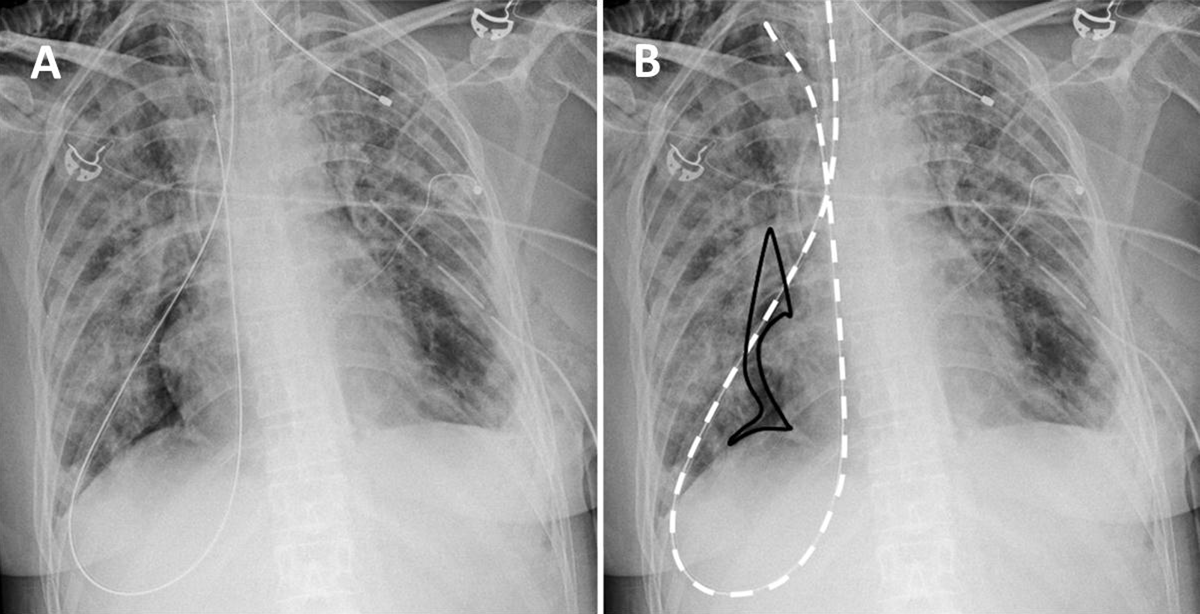

A 36-year-old woman was admitted to the intensive care unit for progressive dyspnea in a context of pulmonary fibrosis. Chest X-ray (Figure 1A) after insertion of a nasogastric tube (NGT) revealed a misplacement with the tube seemingly coursing downwards through the right main stem bronchus before looping in posterior pleural recess and heading toward the right pulmonary apex (Figure 1B, white dotted line). It also showed pneumothorax, manifesting as a right paracardiac radiolucency (black line). Shortly after removing this misplaced NGT, the patient went into cardiac arrest. Aware of the preexistent pneumothorax and in accordance to abnormal auscultation, tension pneumothorax was clinically suspected and thoracic drainage was performed, allowing resuscitation.

Figure 1